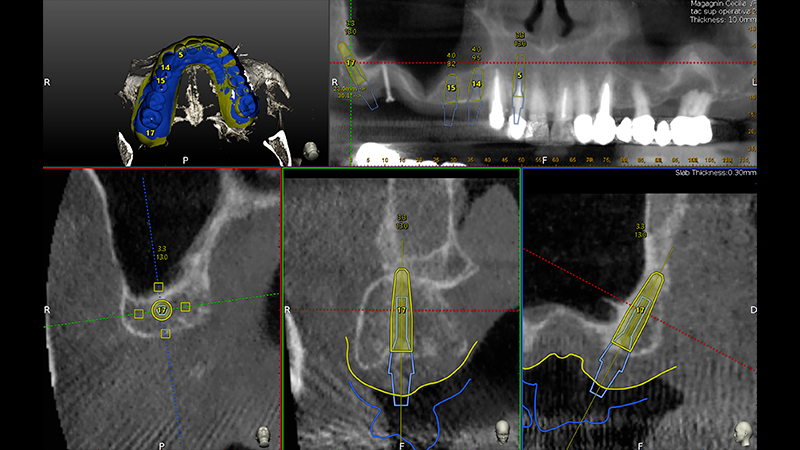

Veniva eseguita la pianificazione del caso con l'utilizzo dell'STL della Biocopia (Fig. 9) e della gengiva guarita (Fig. 10), e di tutti gli impianti: zona 12 con pianificazione post-estrattiva flapless con Socket Shield (Fig. 11), zona 14 (Fig. 12), zona 15 (Fig. 13) e zona pterigoidea (Fig. 14). Dopo la chirurgia (Video 1 e 2), OPT post-operatoria e endorali venivano fatte per valutare il rialzo di seno trans-crestale (Figs. 15, 16, 17, 18).

Pianificazione chirurgica della posizione implantare

Fig. 9 - Pianificazione chirurgica della posizione implantare su Software Navident (Claronav) basandosi sulla posizione dei denti originali mediante sovrapposizione di impronta ottica con e senza i denti (STL). Particolare attenzione è stata posta al parallelismo degli impianti 15 e 14, al corretto posizionamento con tecnica Socket Shield su 12 e alla correzione predefinita di 30° del moncone dell'impianto pterigoideo per mantenere il parallelismo conometrico protesico

Pianificazione chirurgica della posizione implantare su Software Navident

Fig. 10 - Pianificazione chirurgica della posizione implantare su Software Navident (Claronav) basandosi sulla posizione dei denti originali mediante sovrapposizione di impronta ottica con e senza i denti (STL). Particolare attenzione è stata posta al parallelismo degli impianti 15 e 14, al corretto posizionamento con tecnica Socket Shield su 12 e alla correzione predefinita di 30° del moncone dell'impianto pterigoideo per mantenere il parallelismo conometrico protesico

Fig. 11 - Pianificazione chirurgica della posizione implantare su Software Navident (Claronav) basandosi sulla posizione dei denti originali mediante sovrapposizione di impronta ottica con e senza i denti (STL). Particolare attenzione è stata posta al parallelismo degli impianti 15 e 14, al corretto posizionamento con tecnica Socket Shield su 12 e alla correzione predefinita di 30° del moncone dell'impianto pterigoideo per mantenere il parallelismo conometrico protesico

Fig. 12 - Pianificazione chirurgica della posizione implantare su Software Navident (Claronav) basandosi sulla posizione dei denti originali mediante sovrapposizione di impronta ottica con e senza i denti (STL). Particolare attenzione è stata posta al parallelismo degli impianti 15 e 14, al corretto posizionamento con tecnica Socket Shield su 12 e alla correzione predefinita di 30° del moncone dell'impianto pterigoideo per mantenere il parallelismo conometrico protesico

Fig. 13 - Pianificazione chirurgica della posizione implantare su Software Navident (Claronav) basandosi sulla posizione dei denti originali mediante sovrapposizione di impronta ottica con e senza i denti (STL). Particolare attenzione è stata posta al parallelismo degli impianti 15 e 14, al corretto posizionamento con tecnica Socket Shield su 12 e alla correzione predefinita di 30° del moncone dell'impianto pterigoideo per mantenere il parallelismo conometrico protesico

Fig. 14 - Pianificazione chirurgica della posizione implantare su Software Navident (Claronav) basandosi sulla posizione dei denti originali mediante sovrapposizione di impronta ottica con e senza i denti (STL). Particolare attenzione è stata posta al parallelismo degli impianti 15 e 14, al corretto posizionamento con tecnica Socket Shield su 12 e alla correzione predefinita di 30° del moncone dell'impianto pterigoideo per mantenere il parallelismo conometrico protesico